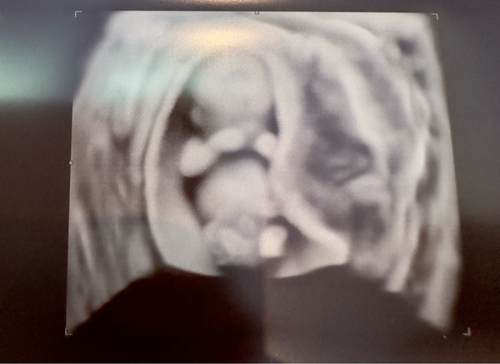

Hey bin in Ssw 11 und habe letzte Woche das Herz meiner 2 Wunder schlagen sehen

12+4 🥰